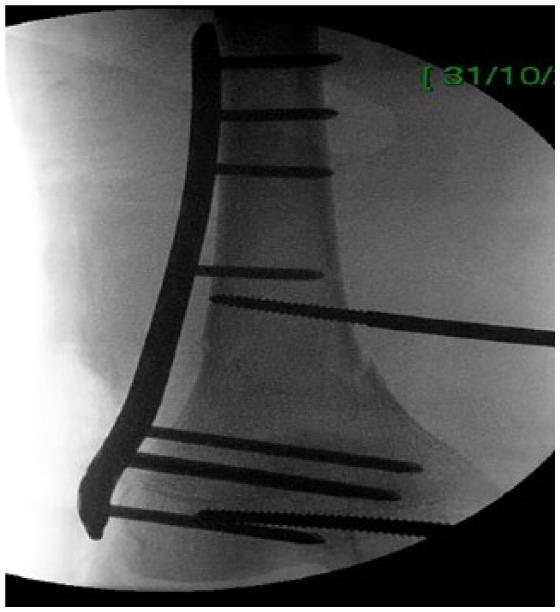

. Pediatric femoral supracondylar fractures are difficult to reduce by either closed or open reduction. The abnormal muscle forces around the knee tend to significantly displace the distal short metaphyseal fragment. We describe a novel technique utilizing the combination of a temporarily intraoperative external fixation in order to achieve and maintain the reduction followed by internal fixation. . Three male patients younger than 16 years of age were operated in our department. The fractures were defined as pathological in 2 patients. In order to facilitate and maintain fracture reduction, an external fixator was temporarily used intraoperatively; once the fractures were internally fixed, the fixator was removed. . Anatomical reduction was achieved in all patients. In an average follow-up of 2 years, all the fractures are solidly healed and the various bone lesions are healing. All patients have returned to regular physical activity. . Difficult supracondylar femur fractures in children are easier to manipulate and reduce with the assistance of an intraoperative external fixator. Once the fracture is internally fixed and stable, the external fixator is removed.

小儿股骨髁上骨折无论是闭合复位还是切开复位都很难。膝关节周围异常的肌肉力量往往会使远端短干骺端骨折块明显移位。我们描述了一种新技术,即术中临时使用外固定架以实现并维持骨折复位,随后进行内固定。

我们科室对3名16岁以下男性患者进行了手术。其中2例骨折被定义为病理性骨折。为了便于并维持骨折复位,术中临时使用了外固定架;一旦骨折进行了内固定,就拆除固定架。

所有患者均实现了解剖复位。平均随访2年,所有骨折均牢固愈合,各种骨病变也在愈合。所有患者均已恢复正常体育活动。

儿童难处理的股骨髁上骨折在术中外固定架的辅助下更易于操作和复位。一旦骨折进行了内固定且稳定,就拆除外固定架。